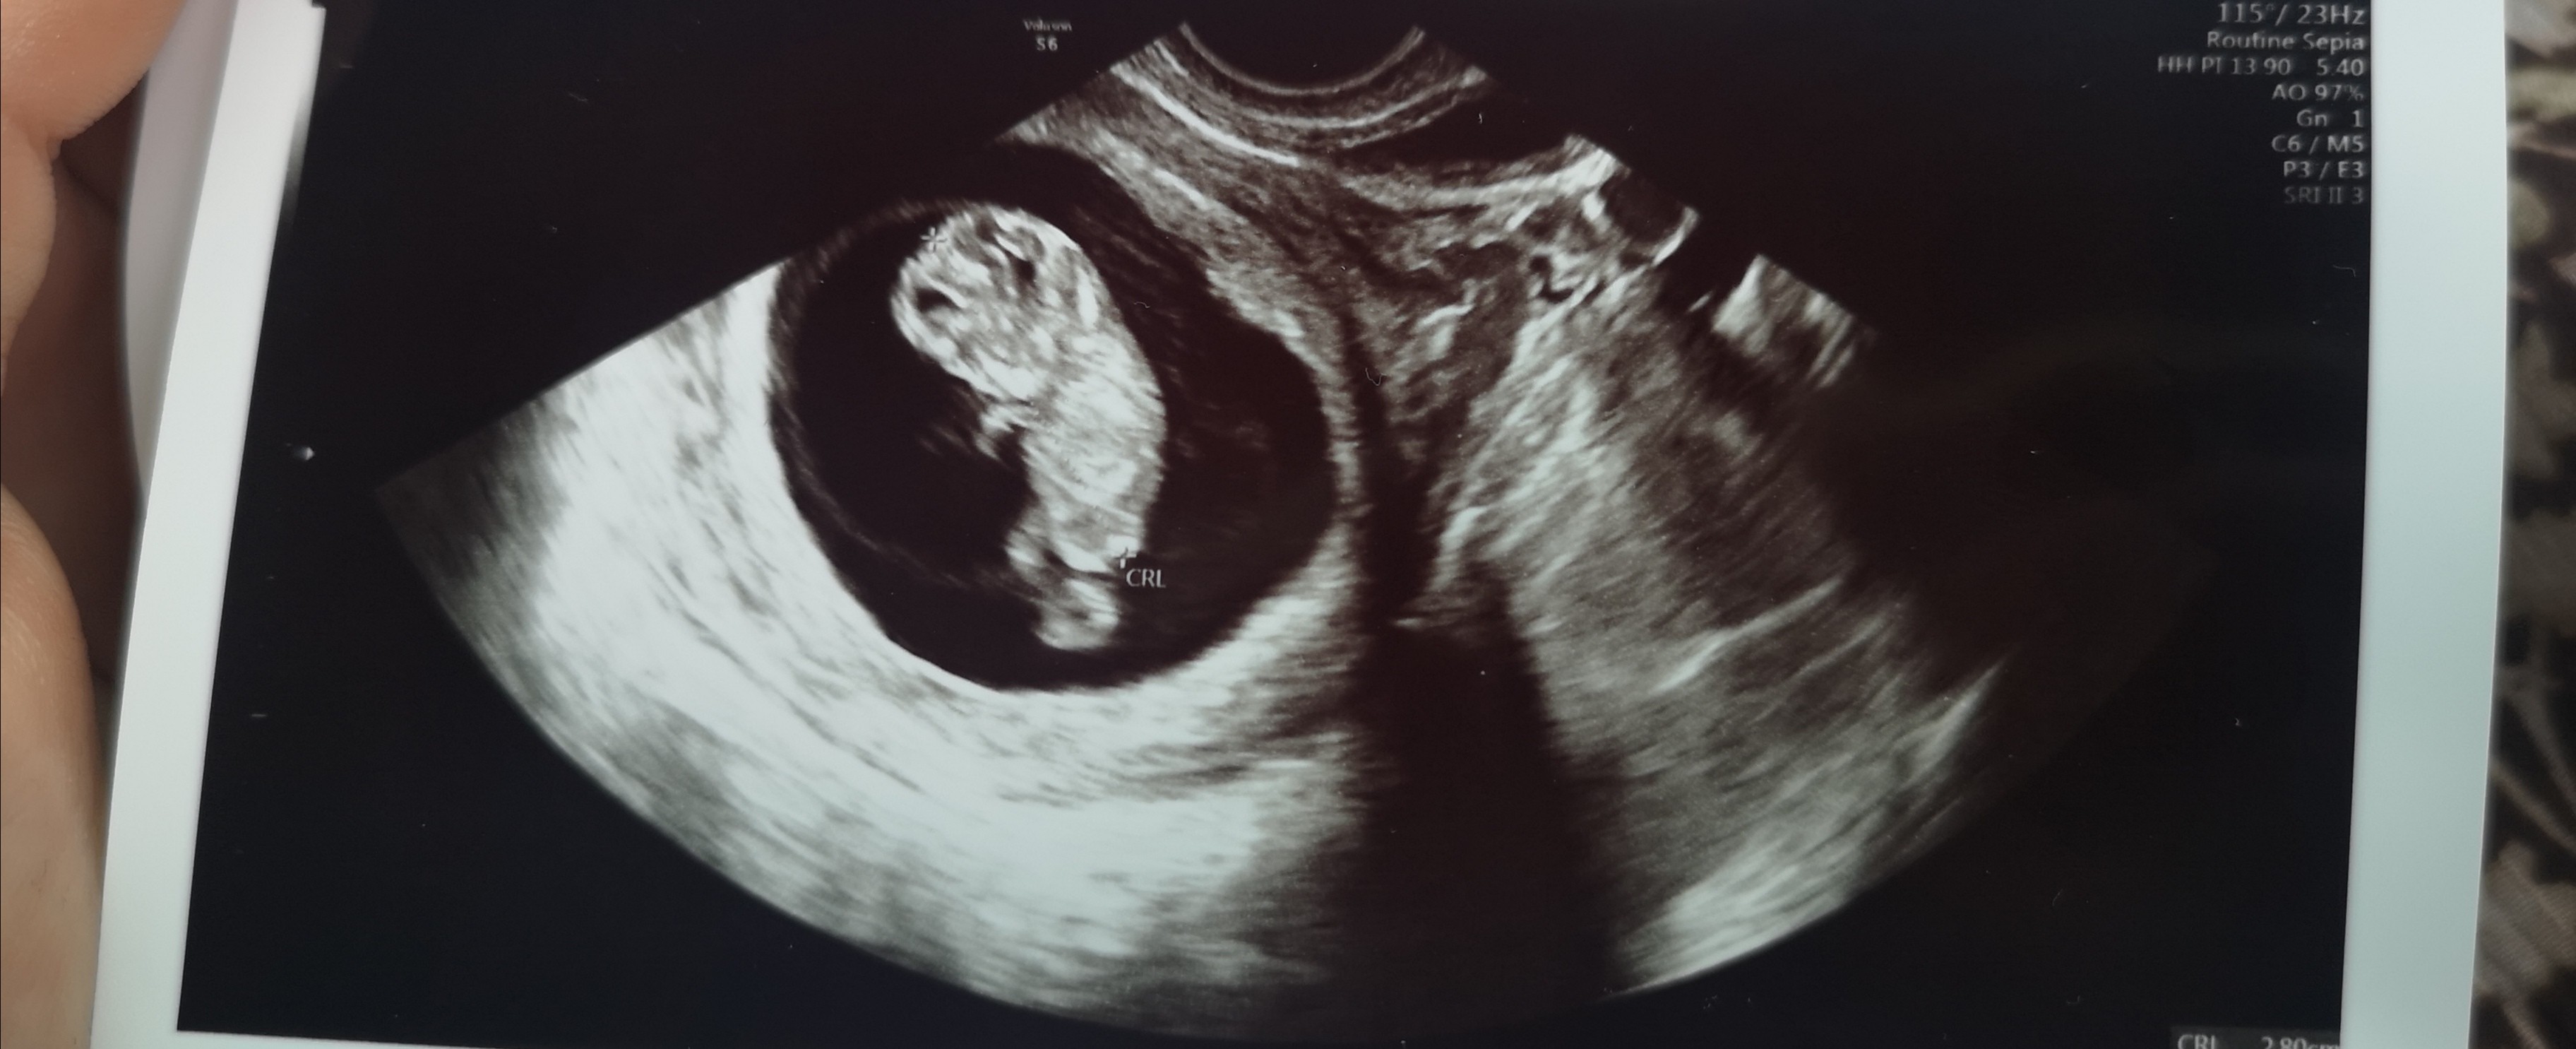

Piękne bobo, jak trzeba to leż, dobrze że p. doktor taka zaangażowanaHej dziewczyny tak mi nie dawały spokoju te plamienia że faktycznie przyspieszyłam wizytę i jestem już po, mamy 11tc serduszko bije, zobaczyłam fasolę jak macha rączkami, niesamowite uczucie, plamienie nadal nie wiaodmo skąd, zwiekszono mi duphastron na 3x 2 tab. (mam nadzieję że to nie zaszkodzi bo jakoś chciałam uniknąć w ciąży jakichkolwiek dodatkowych leków mimo że mam IO i PCOS i niedoczynnośc tarczycy) moja gin zrobiła dodatkowe badanie jakiś wymaz żeby zobaczyć czy to może jakaś bakteria wywołuje plamienia (tanio nie było ale cóż się nie robi) no i mam nawet nie sprzątać domu aż tak mam się oszczędzać. Mam nadzieję że tylko przez 1 trymestr a nie całą ciążę będę musiała leżeć bo już mnie krzyże bolą![]()

Flaczki się w górę przesuwają robią miejsce na maciczkeA swoją drogą dziwne to nie ze dzidzia ma ok 6cm a brzuszki już takie spore niby macica jest nisko a brzuszek okrąglutki![]()